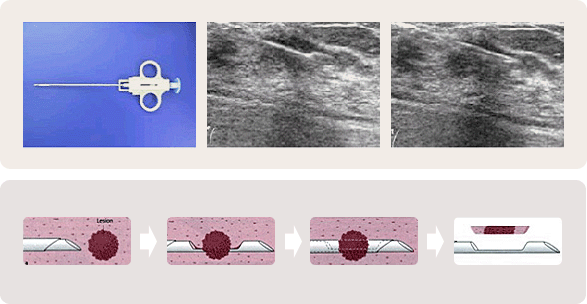

맘모톰은 굵은 바늘을 병소에 넣고 진공흡입기를 작동하여 바늘안으로 조직을 끌어들인 후 바늘내부의 회전칼을 작동시켜 자동으로 병변을 잘라 유방밖으로 배출시키는 방법입니다.